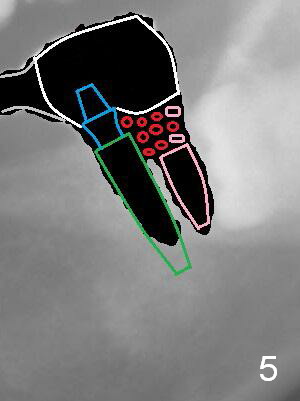

A 35-year-old lady (YL) has periodic nocturnal pain of the lower left quadrant.  There is open buccal margin at the abutment of #18 (Fig.1 (from panoramus)).  When the pontic and the retainer are removed (Fig.2), there is a large buccal subgingival carious lesion at the tooth #18.  The latter has 2 roots, although close to each other.  If the extraction turns out to be difficult, section the tooth (Fig.3 red line (no antibiotic)).  To avoid contacting the tooth #17, place an implant at the mesial socket of #18 (Fig.5,7).  Although it appears that the tooth #20 has no periapical radiolucency (Fig.6,7), the crown will be removed for diagnosis.  A 3-unit provisional will be fabricated after an implant is placed at #19 (Fig.7,8) in the same appointment.